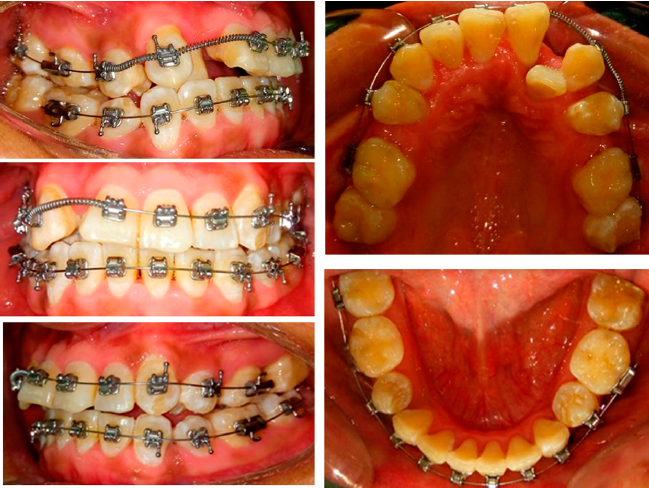

Se realizaron extracciones de los dientes 15, 25, 18, 28, 38 y 48. Se colocaron brackets metálicos, aparatología CCO 0.022” X 0.028” y arcos de Nitinol 0.014” en las arcadas superior e inferior para iniciar con la alineación y nivelación. También se ocuparon resortes abiertos de NiTi para incluir el diente 12 (Figura 4). Posteriormente se colocaron arcos 0.016” x 0.022” Nitinol en las arcadas superior e inferior para continuar con la alineación y nivelación. También se indicaron resortes abiertos y ligadura metálica para distalizar los caninos y lograr clases caninas y molares ideales. Se colocaron botones linguales en el primer segundo premolar superior e inferior izquierdo con elásticos para descruzar mordida.